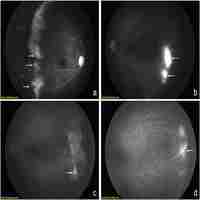

| Abstract | Background Retinopathy of Prematurity (ROP) is one of the most common causes of childhood blindness worldwide. Comparisons of anti-VEGF and laser treatments in ROP are relatively lacking, and the data are scattered and limited. The objective of this meta-analysis is to compare the efficacy of both treatments in type-1 and threshold ROP. Methods A comprehensive literature search on ROP treatment was conducted using PubMed and Embase up to March 2017 in all languages. Major evaluation indexes were extracted from the included studies by two authors. The fixed-effects and random-effects models were used to measure the pooled estimates. The test of heterogeneity was performed using the Q statistic. Results Ten studies were included in this meta-analysis. Retreatment incidence was significantly increased for anti-VEGF (OR 2.52; 95% CI 1.37 to 4.66; P = 0.003) compared to the laser treatment, while the incidences of eye complications (OR 0.29; 95% CI 0.10 to 0.82; P = 0.02) and myopia were significantly decreased with anti-VEGF compared to the laser treatment. However, there was no difference in the recurrence incidence (OR 1.86; 95% CI 0.37 to 9.40; P = 0.45) and time between treatment and retreatment (WMD 7.54 weeks; 95% CI 2.00 to 17.08; P = 0.12). Conclusion This meta-analysis indicates that laser treatment may be more efficacious than anti-VEGF treatment. However, the results of this meta-analysis also suggest that laser treatment may cause more eye complications and increase myopia. Large-scale prospective RCTs should be performed to assess the efficacy and safety of anti-VEGF versus laser treatment in the future. |